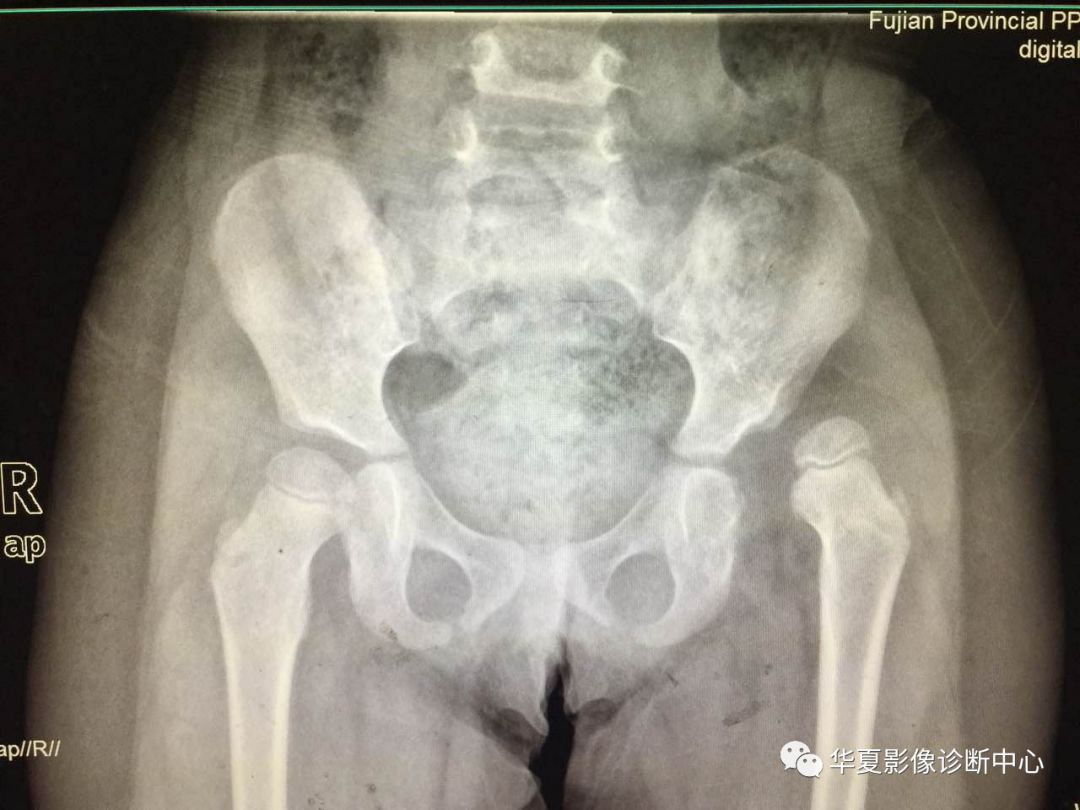

上图:骨盆正位

2.骨盆平片测量法

如图所示两侧髋臼Y形软骨连成为Hilg-eneriner线,简称为H线,股骨上端距H线之距离为上方间隙。股骨上端鸟嘴距坐骨支外缘为内侧间隙,正常均值上方间隙为9.5mm,内侧间隙为4.3mm。若上方间隙小于8.5mm,内侧间隙大于5.1mm应怀疑髋关节脱位。若上方间隙小于7.5mm,内侧间隙大于6.1mm可诊断为髋关节脱位,此法简易可靠。

3.Perkin象限

当股骨头骨骺核出现后可利用Perkin象限,即两侧髋臼中心连一直线称为H线,再从髋臼外缘向H线做一垂线(P),将髋关节划分为四个象限,正常股骨头骨骺位于内下象限内。若在外下象限为半脱位,在外上象限为全脱位。

新生儿正常股骨上端鸟嘴状突起位于内下象限内。若在外下象限为半脱位,在外上象限为全脱位。

股骨头预测骨骺法

即以股骨颈上缘为底边,作一等边三角形,三角形顶点为预测股骨头骨骺,再结合Perkin方格法判断。